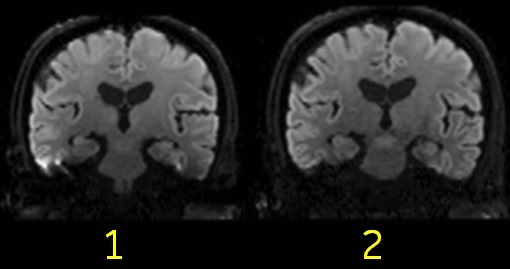

| Number | Description |

|---|---|

| 1 | MUSE de-selected. Note the blurring and susceptibility artifacts. |

| 2 | MUSE selected from the PSD/Application screen. |